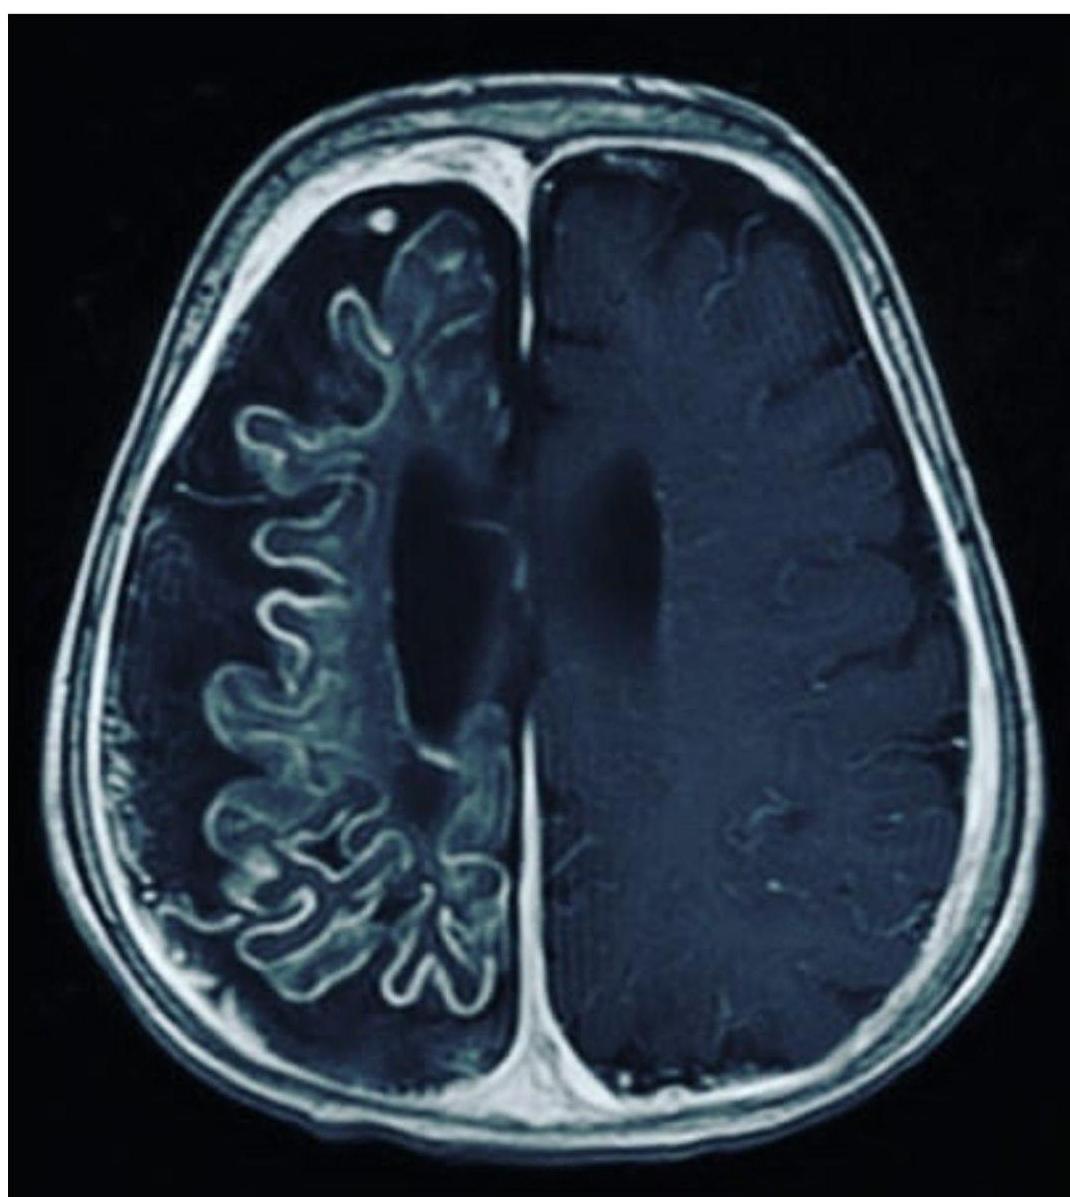

- Best Diagnostic Study: Brain MRI with gadolinium contrast (demonstrates leptomeningeal angioma).

- Brain Atrophy & Calcification: Underlying brain becomes atrophic and calcified (“Tram track” calcification).

- Leptomeningeal Angioma: Vascular anomaly of the leptomeninges on the ipsilateral side.